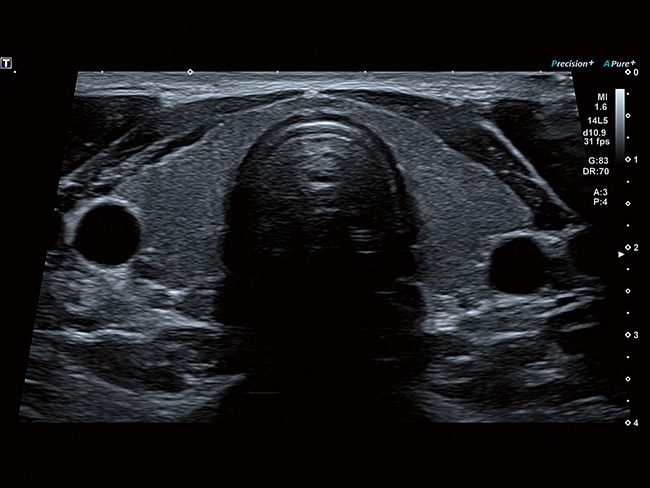

Отличная цветопередача с высокой детализацией и четкостью изображения. Устройство подходит для профессионального использования в частных кабинетах и крупных медицинских центрах. Комплектация сканера применима для самых разных исследований. Широкий диапазон прикладного клинического программного обеспечения высокоэффективен для общих исследований, сердечно-сосудистых, гинекологических, ортопедических, урологических.

Aplio a550 может работать с линейным матричным датчиком и поддерживает новейшие монокристаллические датчики. Также Aplio a550 поддерживает большое количество дополнительных опций, таких как - SMI, Компрессионная эластография, Эластография сдвижной волны, Smart Fusion, исследования с использованием контраста (CEUS), 3D реконструкции в реальном времени (4D), функции автоматической оценки подвижности миокарда и фракции выброса.